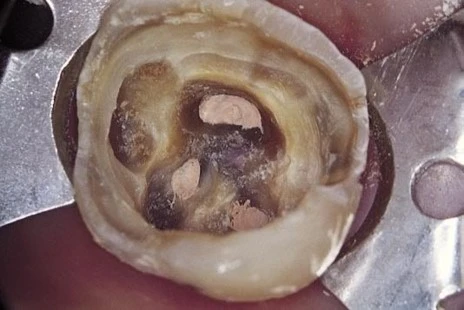

hình ảnh bị mũi khoan trụ ấn vào

Hình ảnh sàn tủy bị mũi khoan trụ lấn vào